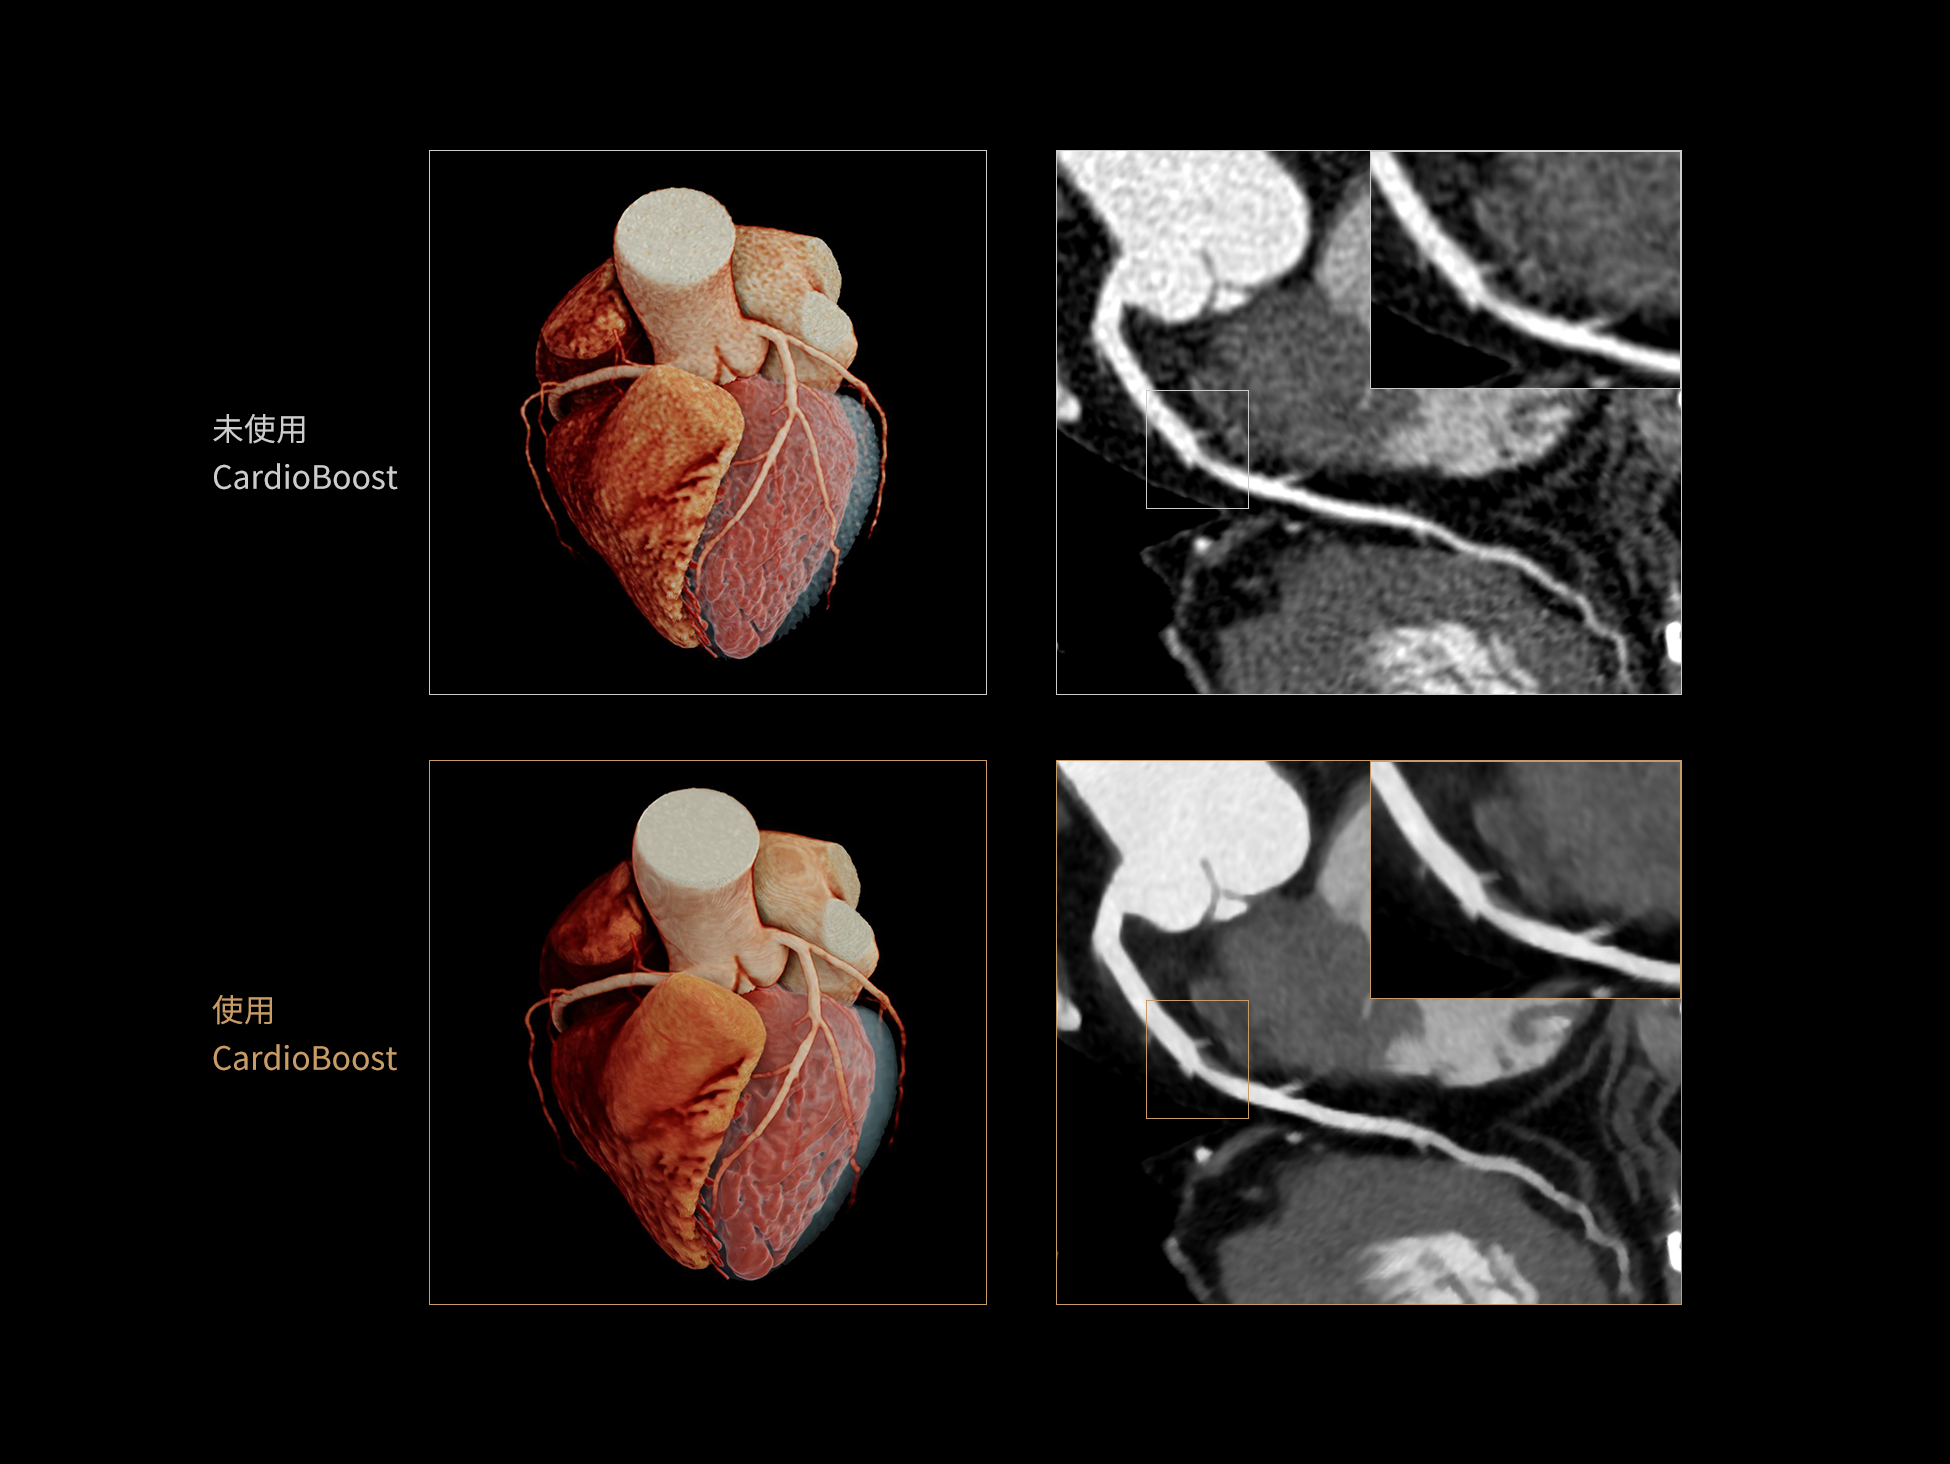

CardioBoost:专属网络设计,重塑心脏影像表现

目前心脏的 CT 检查还存在辐射剂量偏高、空间分辨率不足、 致密钙化伪影影响冠脉狭窄程度评估等方面的限 制[1][2]。CardioBoost 技术专为心脏 CT 高清成像而开发,通过 3D 神经网络的深度学习技术,利用先进的注意力机制在识别关键成像特征方面的出色表现,能够精确地聚焦于斑块、支架以及微小血管等关键细节,清晰展示这些结构与冠脉血管的边界,从而显著提高诊断的准确性,并提升医生的诊断信心。创新的 CardioBoost 心脏图像重建算法,不仅实现了图像清晰度的提升和伪影的去除,更能在减少辐射剂量的同时,保证心脏图像的高质量和图像纹理的自然。

CardioBoost核心创新

采用 3D 神经网络的空间结构优势与精细的组织分类能力,CardioBoost 技术优化了组织对比,高清展示血管斑块,使斑块与血管边缘的轮廓清晰可辨,提升斑块诊断与评估的精确性。

借助 3D 神经网络设计、空间注意力机制聚焦与特征强化作用,CardioBoost技术提升图像的空间分辨率,实现冠脉支架的高清成像,对支架形态与管腔通畅度的评估更精准。

CardioBoost 整合先进的 3D 神经网络和空间注意力机制,大幅增强数据处理的速度与精确度。该技术能有效抑制由致密钙化引起的晕状伪影,清晰展现钙化斑块的原始结构和大小,对冠脉狭窄的评估更加精确可靠。

uOmnispace 提供完整的三维成像与高级可视化工具套件,覆盖全科放射、肿瘤、心脏、神经等多学科临床应用场景。借助智能算法(如自动分割、结构提取与标注),大幅减少人工干预,加速图像分析过程。满足多样化的诊断需求,助力医生在复杂病例中做出更有信心的决策。

超真实渲染(Hyper Realistic Rendering,HRR)可将医学影像数据转化为高度真实、细节丰富的三维数字可视图像。相比传统VR渲染,HRR在解剖结构与图像细节的还原上更为精准,助力临床直观地理解病灶特征与组织关系,更加适用于术前规划、教学演示及患者沟通。

HRR超真实物理渲染:精准还原解剖细节的三维可视化技术